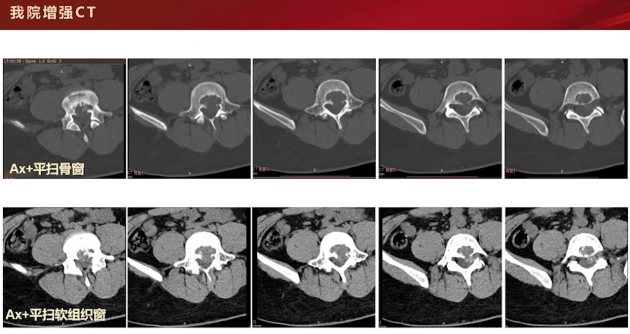

初次CT平扫显示,L5椎体后缘局部骨质密度减低,病灶边缘可见硬化边,无明显骨膜反应及软组织肿块。

增强CT检查,在骨窗和软组织窗下可见L5后缘局部膨胀性骨质破坏,内缘呈扇贝样压迹改变,仍无明显骨膜反应。平扫时,病灶内可见斑斑点点高密度影,性质待定,可能为残存骨嵴、软骨源性钙化或骨化表现。该病例主要累及L5椎体,附件未见明显受累。增强扫描呈轻度强化,矢状位和冠状位可见病灶主要累及椎体,未累及附件。